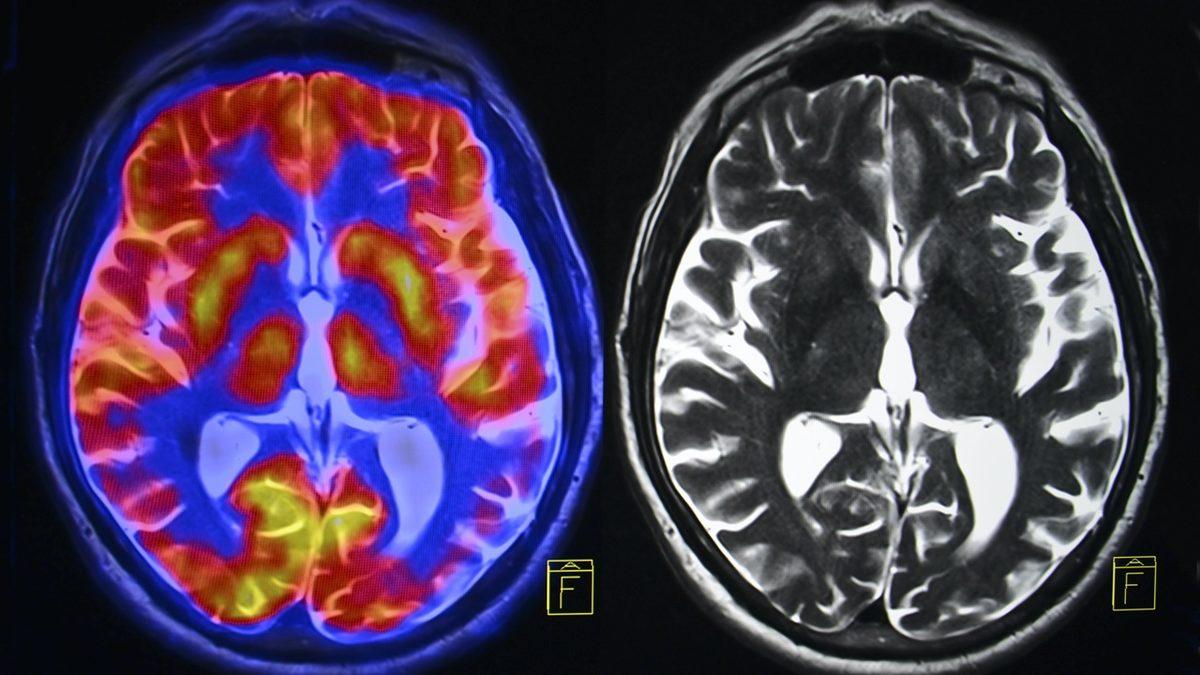

Beyin görüntüleme çalışmaları, teknolojinin gelişmesiyle birlikte ilerledi. Manyetik Rezonans (MR), Difüzyon Tensor Görüntüleme(DTI), Pozitron emisyon tomografi (PET) gibi görüntüleme teknikleri beyinde gerçekleşmiş olan ve psikolojik bozukluğa yol açabilecek yapısal ve işlevsel bozukluklar hakkında bilgi veriyor.

Fakat burada asıl önemli olan, "beyinde değişimler olduğu için mi bu bozuklukların yaşandığı yoksa bu bozukluklar zaten var olduğu için mi beyindeki bu değişimler yaşandı?" sorusunun cevabıdır. Bu sorunun cevabı, gelinen aşamada henüz bilinemiyor. Aynı şey beyindeki dopamin, glutamat, serotonin, GABA gibi nörotransmitterler için de geçerli. Örneğin depresyon gibi bozukluklarda hastanın serotonin seviyesinin düşük olduğu bilinir ve verilen antidepresanlarla bunun seviyesi artırılmaya çalışılır ve bu, danışana iyi gelir. Fakat bozukluğun tek nedeni serotonin düşüklüğü müdür, yoksa o bir sonuç mudur?